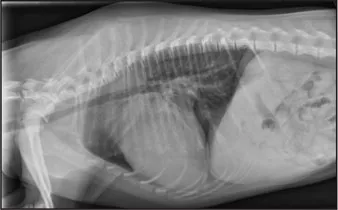

CASE 1.1 A 7-year-old neutered male Labrador Retriever who was hit by a car. You obtain these thoracic radiographs: Figs. 1.1a, b, left and right lateral projections, respectively; Figs. 1.1c, d, ventrodorsal and dorsoventral projections, respectively.

1.1b